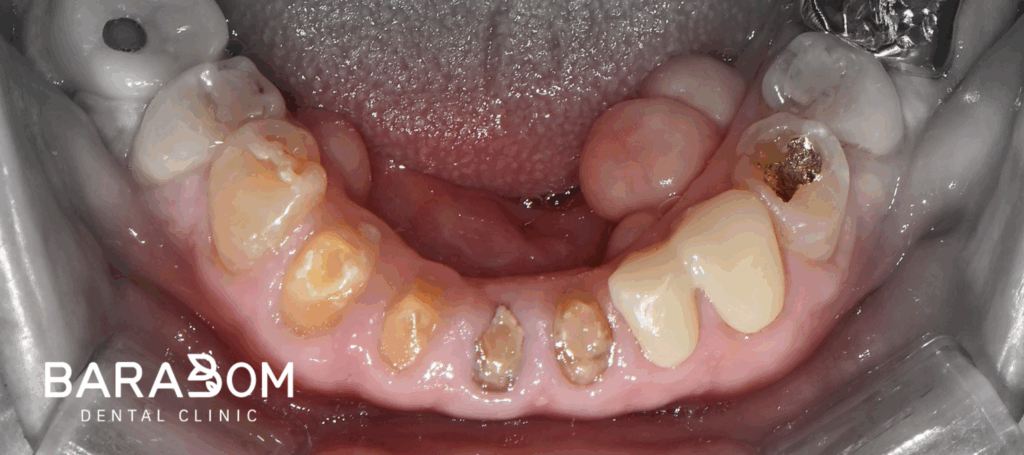

그럼 자주 보철이 탈락하게 되어 불편으로 이어질 수 밖에 없는데, 현재 하악 앞니 뿐만 아니라 어금니도 치아 머리의 길이가 짧은 상태였습니다. 하악 절치부 치관 길이가 매우 짧으며, 상악 절치 구개부와 간격이 불과 2mm 이내였습니다. 현재 상태로써 새로운 보철을 제작하긴 어렵다 판단되고 있습니다.

짧아진 교합 고경을 새로 만들기 위해서는 위아래쪽 어금니에 새로운 보철을 만들어 씌우는 과정이 필요합니다. 그런데 그 과정이 여간 쉬운게 아니며, 경제적인 측면에서 부담이 되기 때문에 닳아서 자주 탈락하는 아래쪽 앞니 부분과 유난히 치관의 길이가 짧은 하악 구치부에만 새로 보철을 제작하여 수복해줌으로써 교합 거상을 진행하는 치료 계획을 세워볼 수 있습니다.

제가 준비한 케이스의 경우에는 양측 첫번째 작은 어금니에는 크라운이 아닌 레진이라는 재료로 수복하는 것만으로도 충분하다 생각되었습니다. #34,44를 제외한 어금니는 크라운 교체를 진행하고 양측 제1소구치에는 레진 수복해줌으로써 보다 경제적으로 치료를 진행해볼 수 있습니다.

앞서 설명드린 것처럼 교합고경을 재건할 때, 여러 사항을 고려하여 신중을 기여해야 됩니다. 하악 구치부 크라운 수복을 진행한 결과, 앞니쪽에 3mm 가량의 공간이 형성되었습니다.